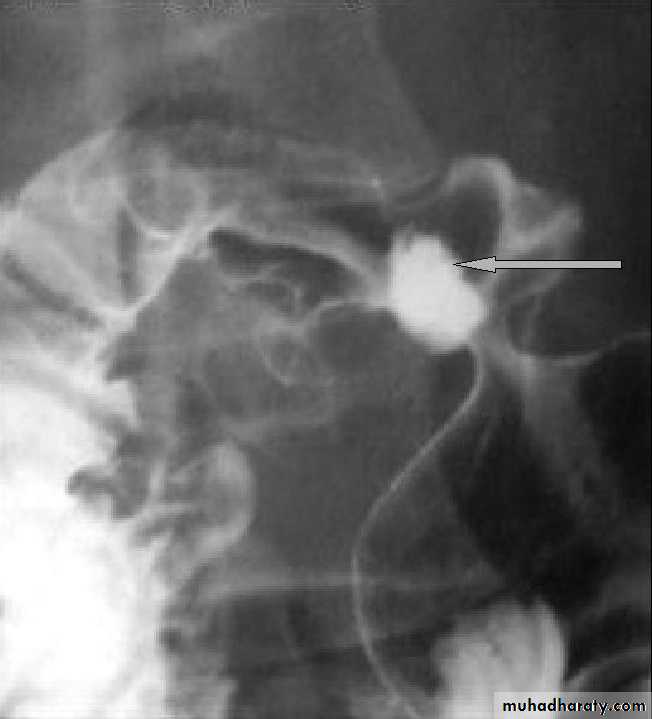

2- Barium studies DU appears as a well-demarcated crater, most often seen in the bulb. Benign GU also appears as a discrete crater with radiating mucosal folds originating from the ulcer margin. Ulcers >3 cm in size or associ. with a mass are more often malignant.